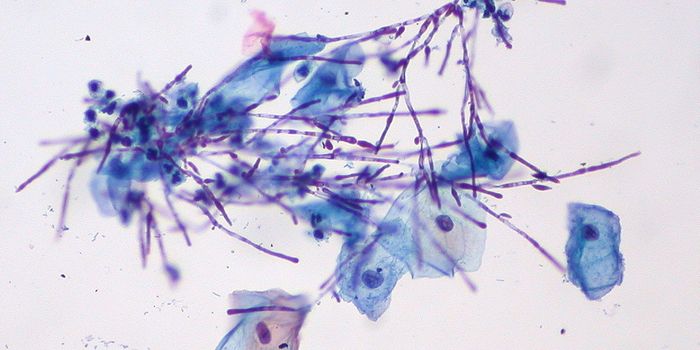

FEB 02, 2017Clinical & Molecular DXA series of fungal-related deaths at the University of Pittsburgh Medical Center may be caused by moldy linens.. The fiv ...